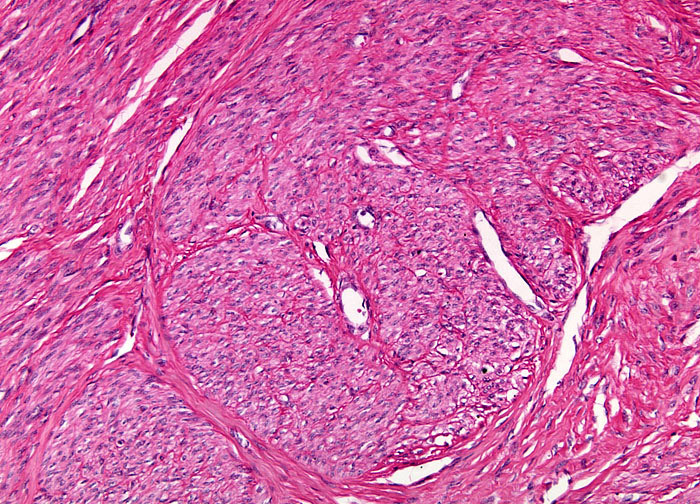

Webpathology.com: A Collection Of Surgical Pathology Images

www.webpathology.com

www.webpathology.com

uterus active webpathology leiomyoma slides pathology leiomyomas comments